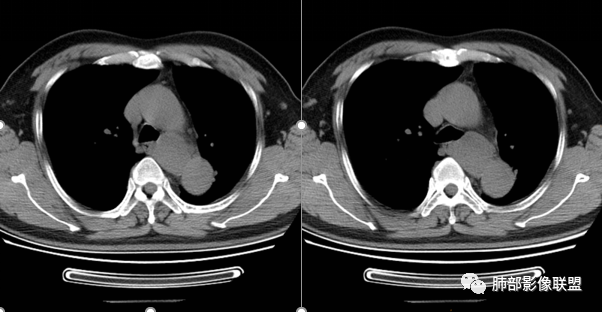

气管、左主支气管后方,食道左侧囊性占位,壁薄且均匀、光滑。气管及左主支气管受压凹陷、变形。

食道也受压变形、移位。

(1)为纵隔囊肿的一种。可发生于纵隔的任何部位,但更常见于中上纵隔。多数与支气管、气管有密切关系,以气管右旁区域及气管隆突下区最多见。

(1)圆形或椭圆形、边缘光滑的病灶,囊壁薄,囊壁可见钙化;由于病变的支气管起源性,囊壁可见属于气管壁的软骨成份.

(2)囊液密度均匀,根据性质的不同而呈不同密度,可为近似水样密度,也可为较高密度,因为囊壁分泌粘液,所以囊内密度一般高于其他纵隔囊肿,CT值多大于20HU甚至超过60HU;